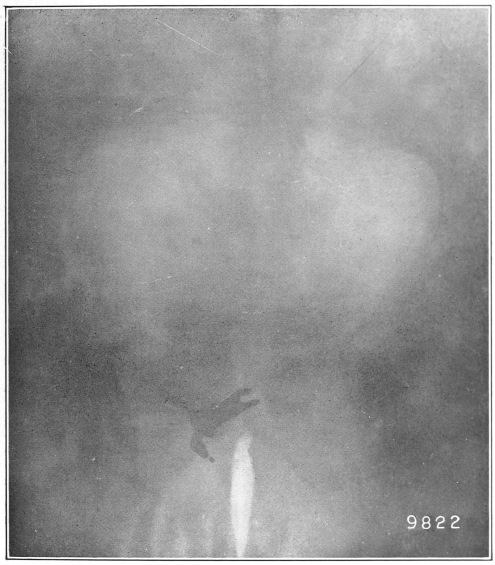

3 I found it more convenient to use the words mucus channel, mucus fistula, etc., in preference to sinus, as they better convey my ideas to the average reader.